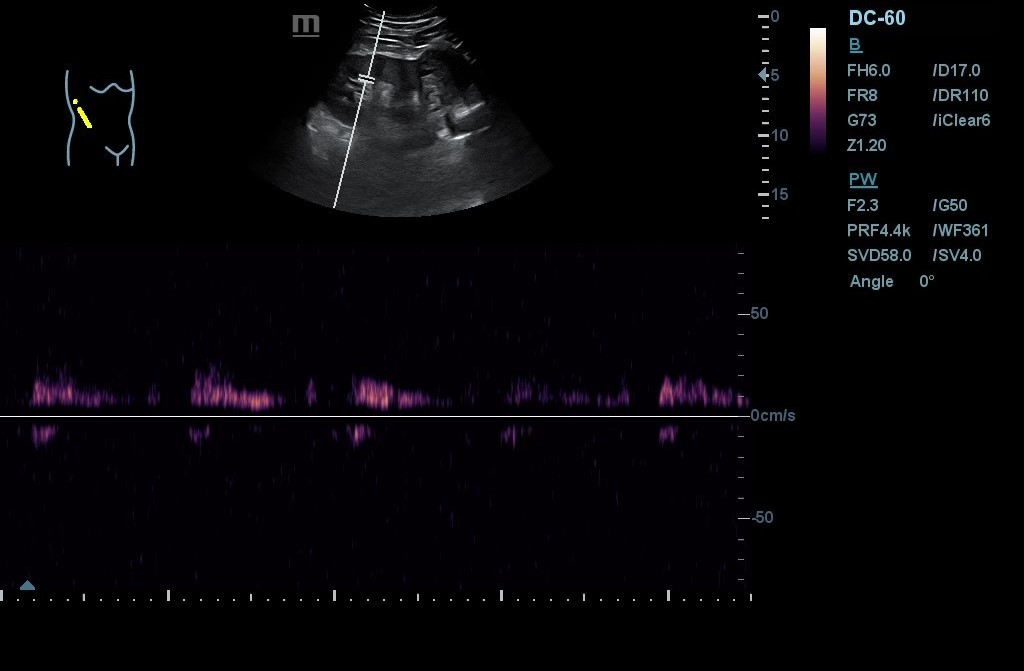

- POCUS: Lesión en polo inferior de riñón derecho (RD) de 6,2 x 5,02 cm de diámetro, con neovascularización y zonas hiperecogénicas. No signos de hidronefrosis. Disminución del flujo venoso con Doppler pulsado. Resultados compatibles con masa renal sólida a filiar. RI sin alteraciones. Jets vesicales presentes. Próstata de contornos regulares y ecogenicidad homogénea. Volumen prostático de 44 cm3.